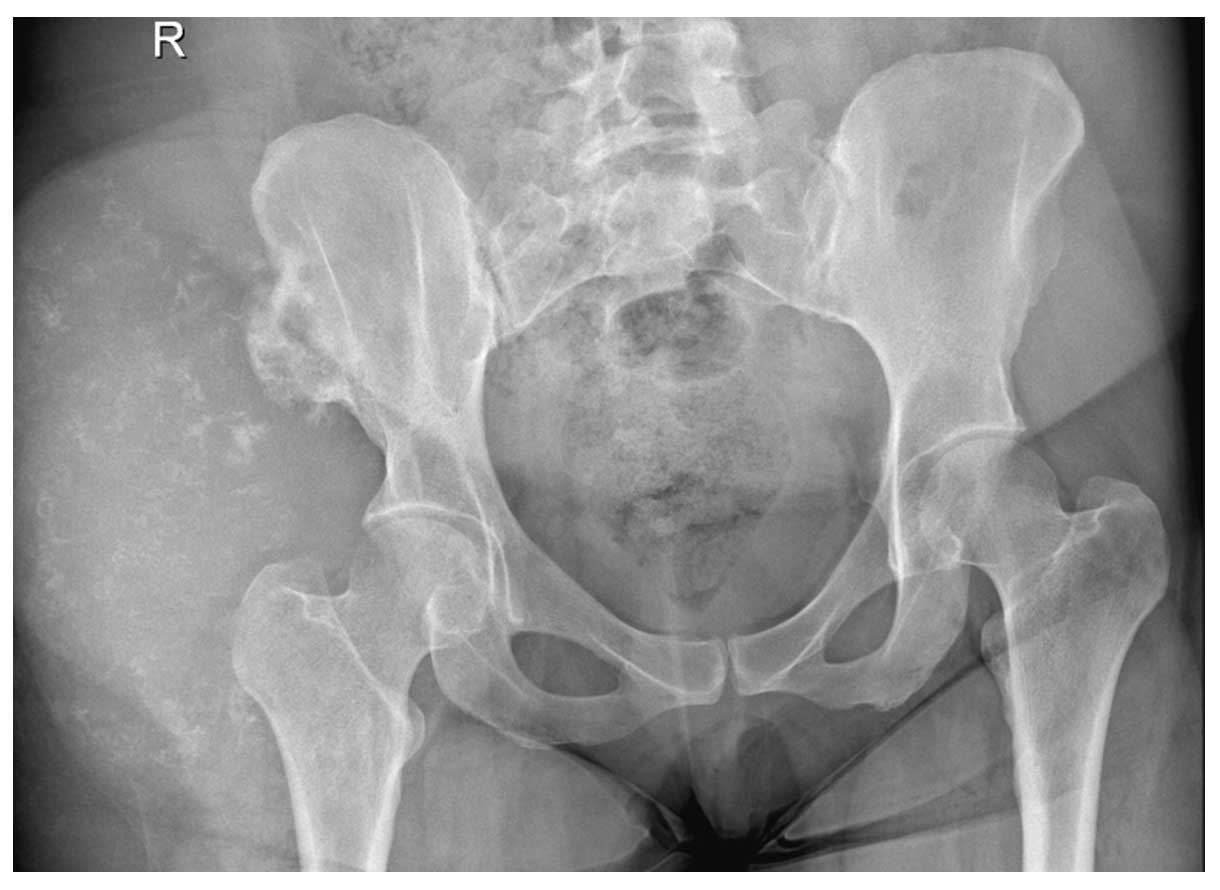

Ameliyat Öncesi: Röntgende sağ iliak kanat dış kısımda yumuşak dokuya uzanım gösteren düzensiz kalsifikasyonlar içeren kitle lezyonu görülmekte.